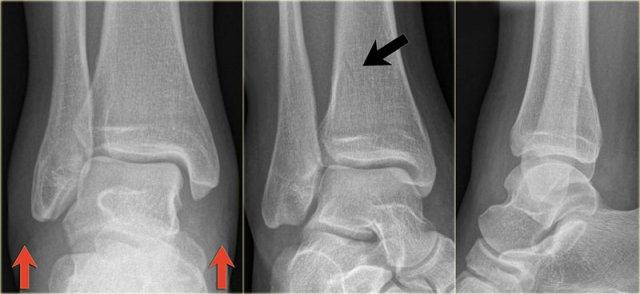

Bác sĩ X-quang quyết định chỉ định CT trước để xác định xem có thực sự có gãy tertius hay không.

Tiếp tục xem hình ảnh CT và bạn sẽ ngạc nhiên.

Hãy cuộn qua các lát cắt.

Thật đáng ngạc nhiên khi một mảnh tertius lớn như vậy lại rất khó nhìn thấy trên phim X-quang.

Cũng lưu ý phù nề phần mềm phía trong gợi ý đứt dây chằng bên trong (mũi tên).

Bạn có thể đoán được đây là loại chấn thương gì không?

Phù nề phần mềm phía trong và gãy tertius đều là dấu hiệu của chấn thương Weber C hoặc chấn thương xoay ngoài – sấp.

Do không thấy gãy xương mác trên phim X-quang cổ chân, phải có gãy xương mác cao.

Khi khám lâm sàng, có phù nề nhẹ phía trong và mặc dù bệnh nhân không than đau ở vùng cao hơn của cẳng chân, vẫn có điểm đau khi ấn vào xương mác.

Vị trí này được đánh dấu và phát hiện đường gãy.

Ca bệnh này minh họa tầm quan trọng của phù nề phần mềm phía trong cũng như dấu hiệu gãy tertius.

Theo phân loại Lauge Hansen, chúng ta có thể kết luận rằng bệnh nhân này đầu tiên bị đứt dây chằng bên trong (giai đoạn 1), tiếp theo là đứt dây chằng chày mác trước (giai đoạn 2), gãy xương mác cao (giai đoạn 3) và cuối cùng là bong mắt cá sau, tức là chấn thương xoay ngoài – sấp (PE) giai đoạn 4.

Trong phẫu thuật, cổ chân được xác định là không vững và vít cố định khớp chày mác đã được đặt vào.

Có chỉ định cố định gãy mắt cá sau vì mảnh gãy chiếm hơn 25% diện khớp của đầu dưới xương chày.